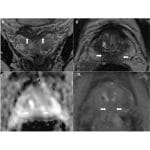

Incidental findings in multiparametric MRI of the prostate

Imaging is an integral part of diagnosis and treatment. Multiparametric MR prostate imaging is primarily done to evaluate the prostate and to identify targets for biopsy. This helps to reduce sampling errors and improve subsequent correct diagnosis and management of prostate cancers. It is called multiparametric imaging as various sequences such as T2W, T1W, DWI, […]